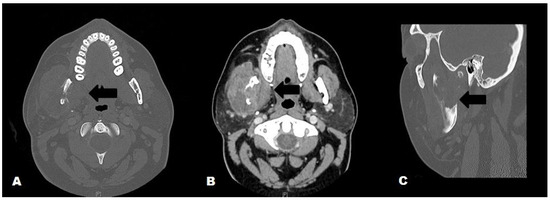

Mandibular Blastomycosis: A Case Report and Review of the Literature

by Fritzie S. Albarillo, Gotam T. Varma and Stephen P.R. MacLeod

Germs 2018, 8(4), 207-213; https://doi.org/10.18683/germs.2018.1148 - 3 Dec 2018

Introduction: Blastomycosis is an endemic mycosis in the United States known to primarily cause pneumonia. However, dissemination to different organs including the musculoskeletal system has been described. Case report: We report a case of mandibular blastomycosis in a healthy patient with no evidence of lung involvement. A 28 year-old female presented with recurrent right mandibular osteomyelitis despite courses of antibiotics and surgical debridement. She eventually underwent right hemimandibulectomy. Budding yeasts visualized on Gomori Methenamine-Silver (GMS) and Periodic acid–Schiff (PAS) were morphologically consistent with Blastomyces dermatitidis, and intra-operative cultures showed growth of mold identified as B. dermatitidis by DNA probe. She was placed on a prolonged course of itraconazole with clinical improvement. We also reviewed the literature and found 5 cases of similar presentation which we briefly summarized in this present case report. Conclusion: Blastomycosis should be considered in patients with recurrent or persistent mandibular osteomyelitis even in immunocompetent individuals. Full article

Show Figures

Figure 1